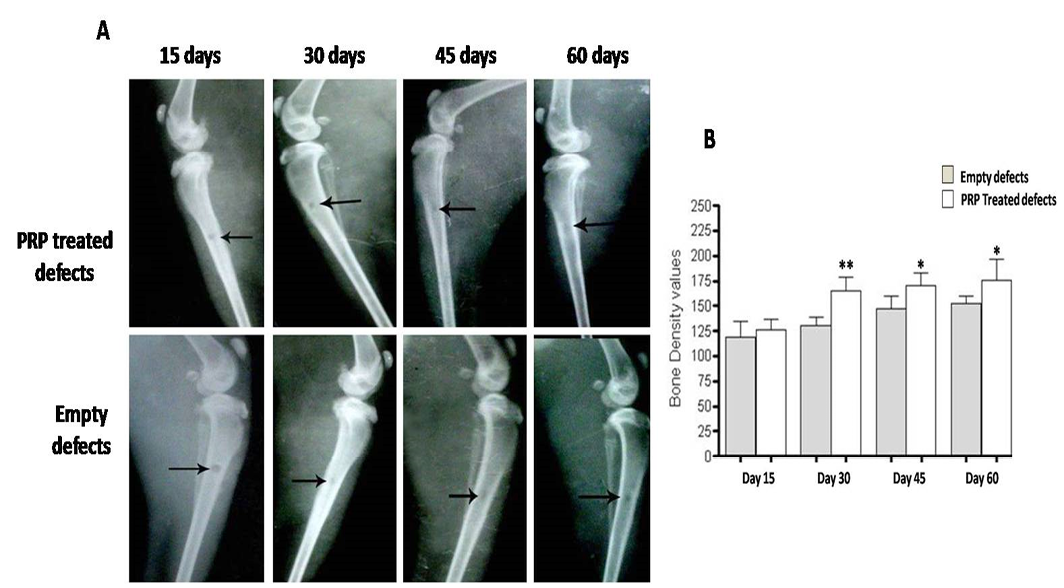

Radiographic evaluation reveals incomplete osseous healing in both PRP- treated and untreated defects (A) with a marked significant increase in radiopacity at 30 days post-injury (B). *P<0.05 and **P<0.01